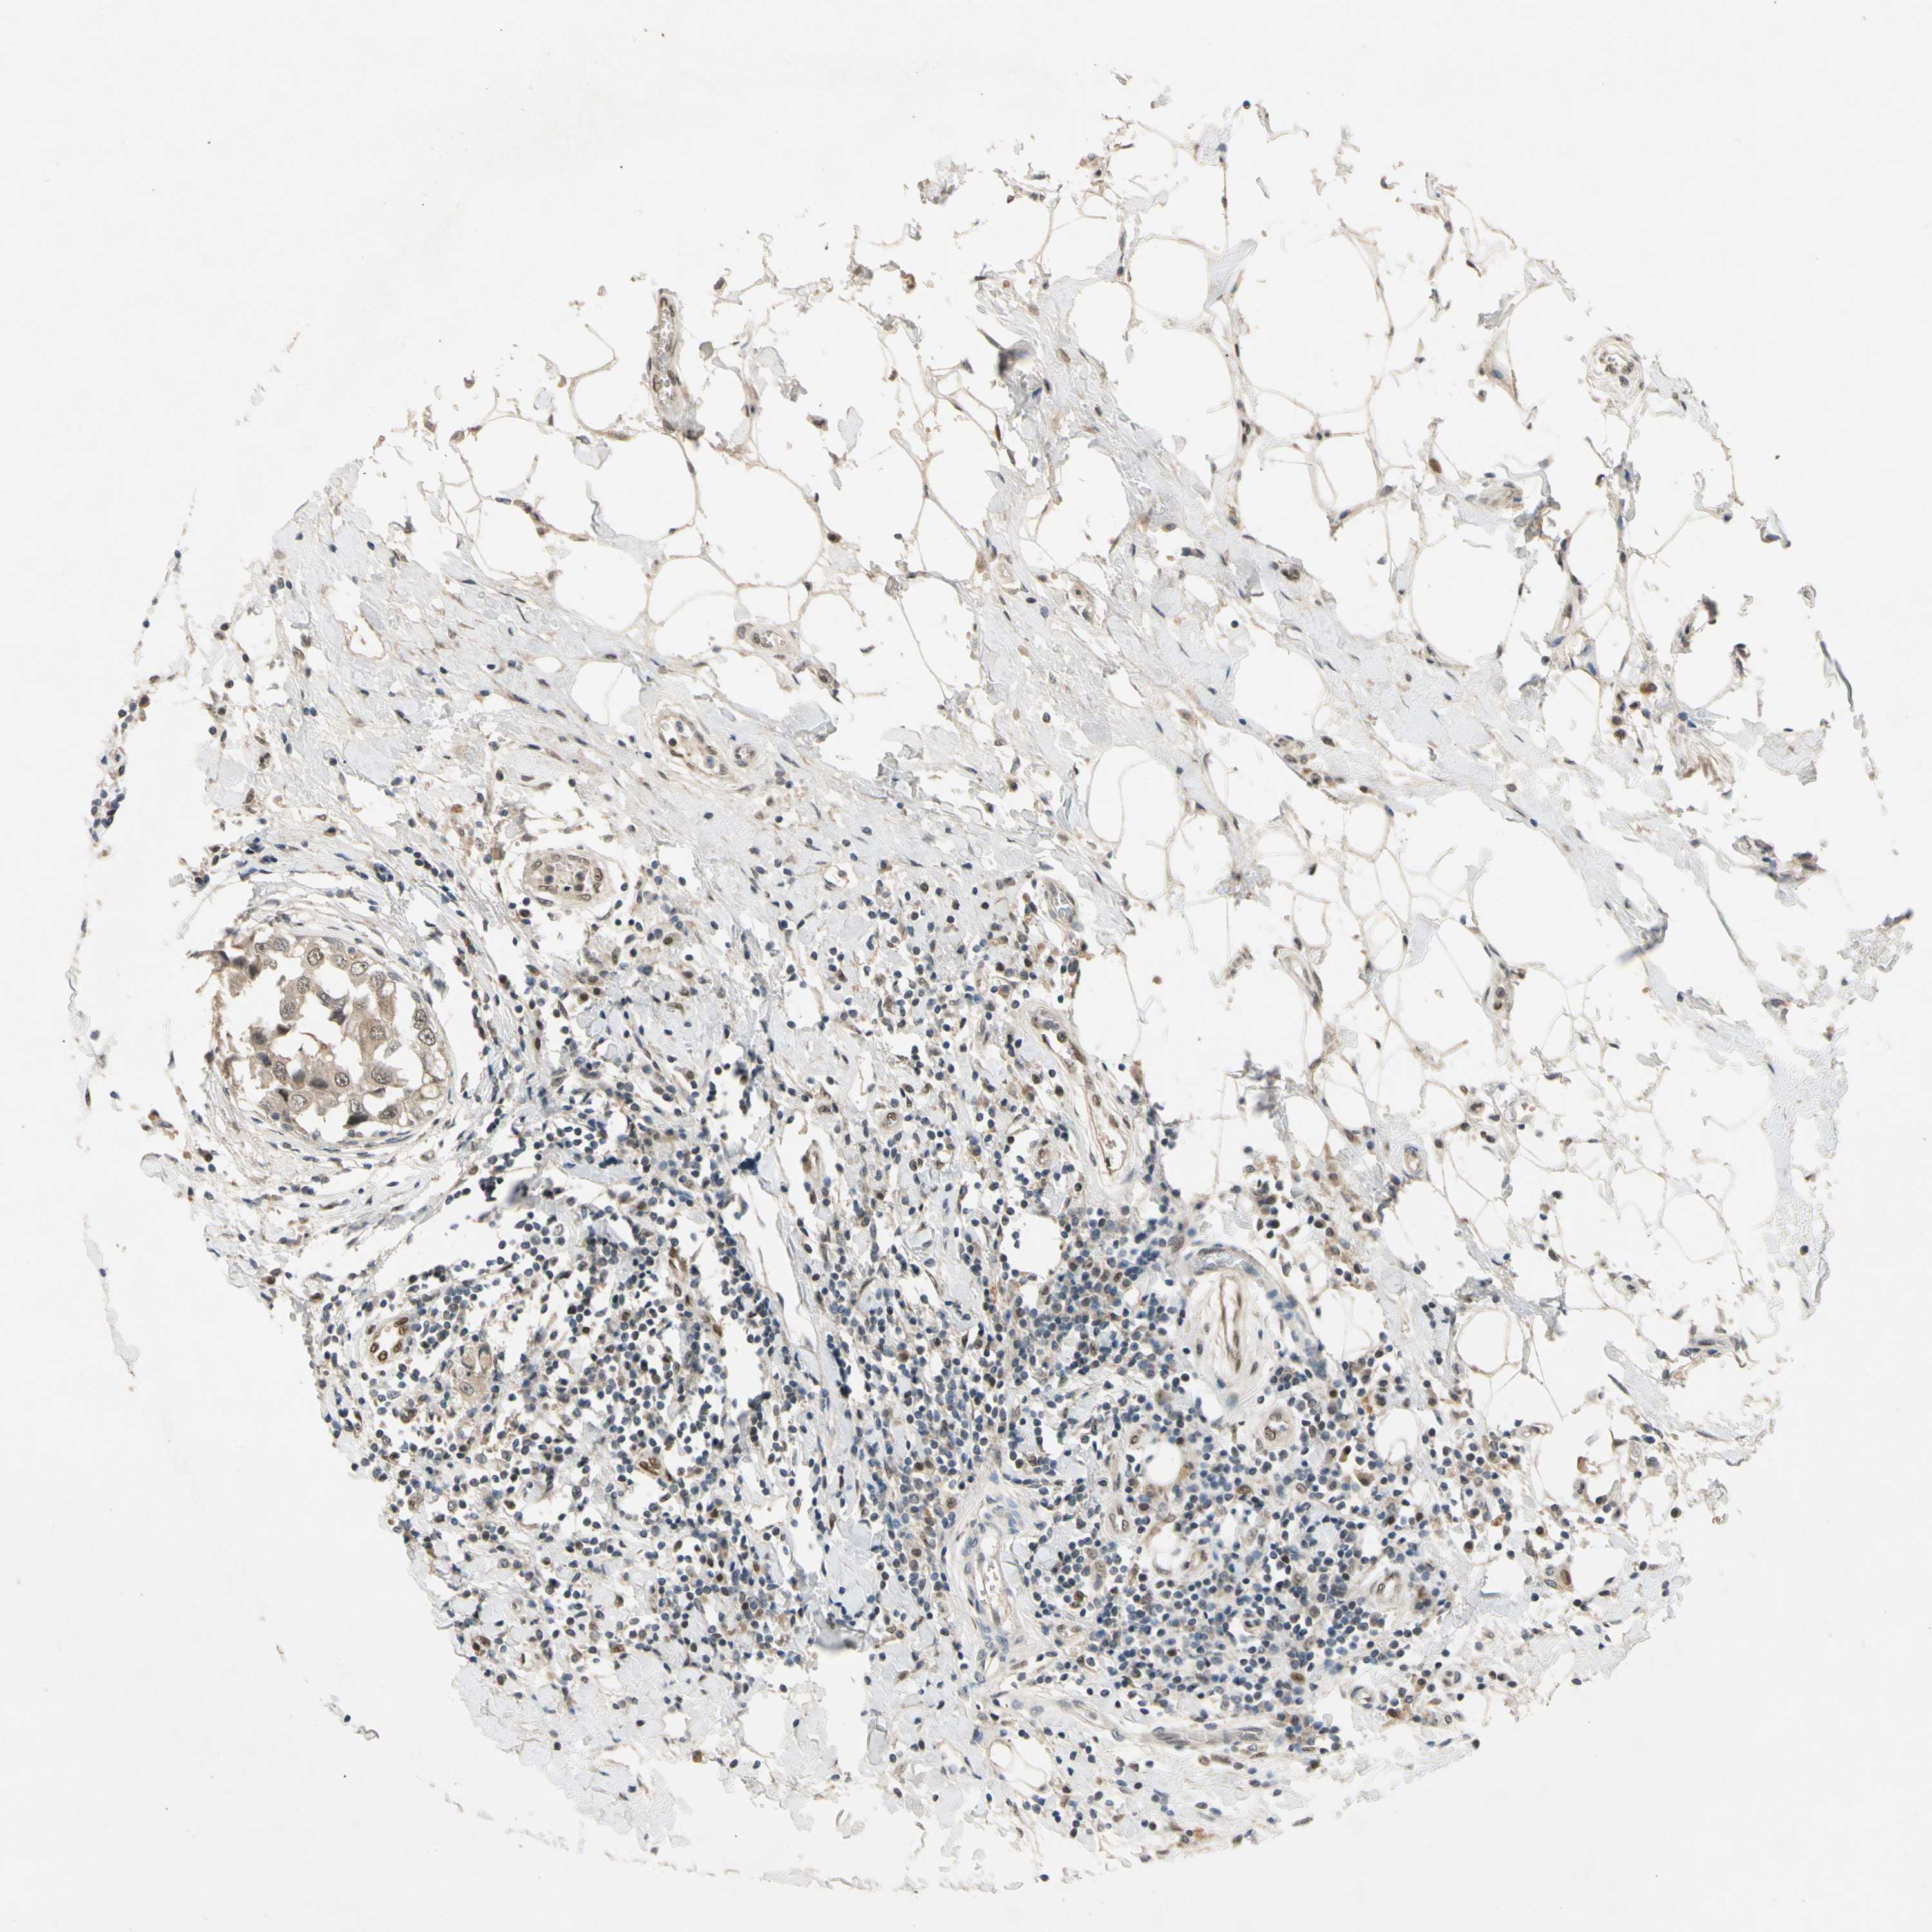

BRCA TCGA BRCA VALIDATION PROTEIN EXPRESSION